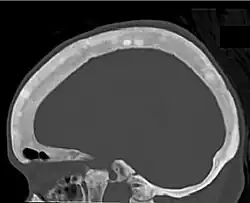

CT shows focal areas of osteosclerosis.[18] -